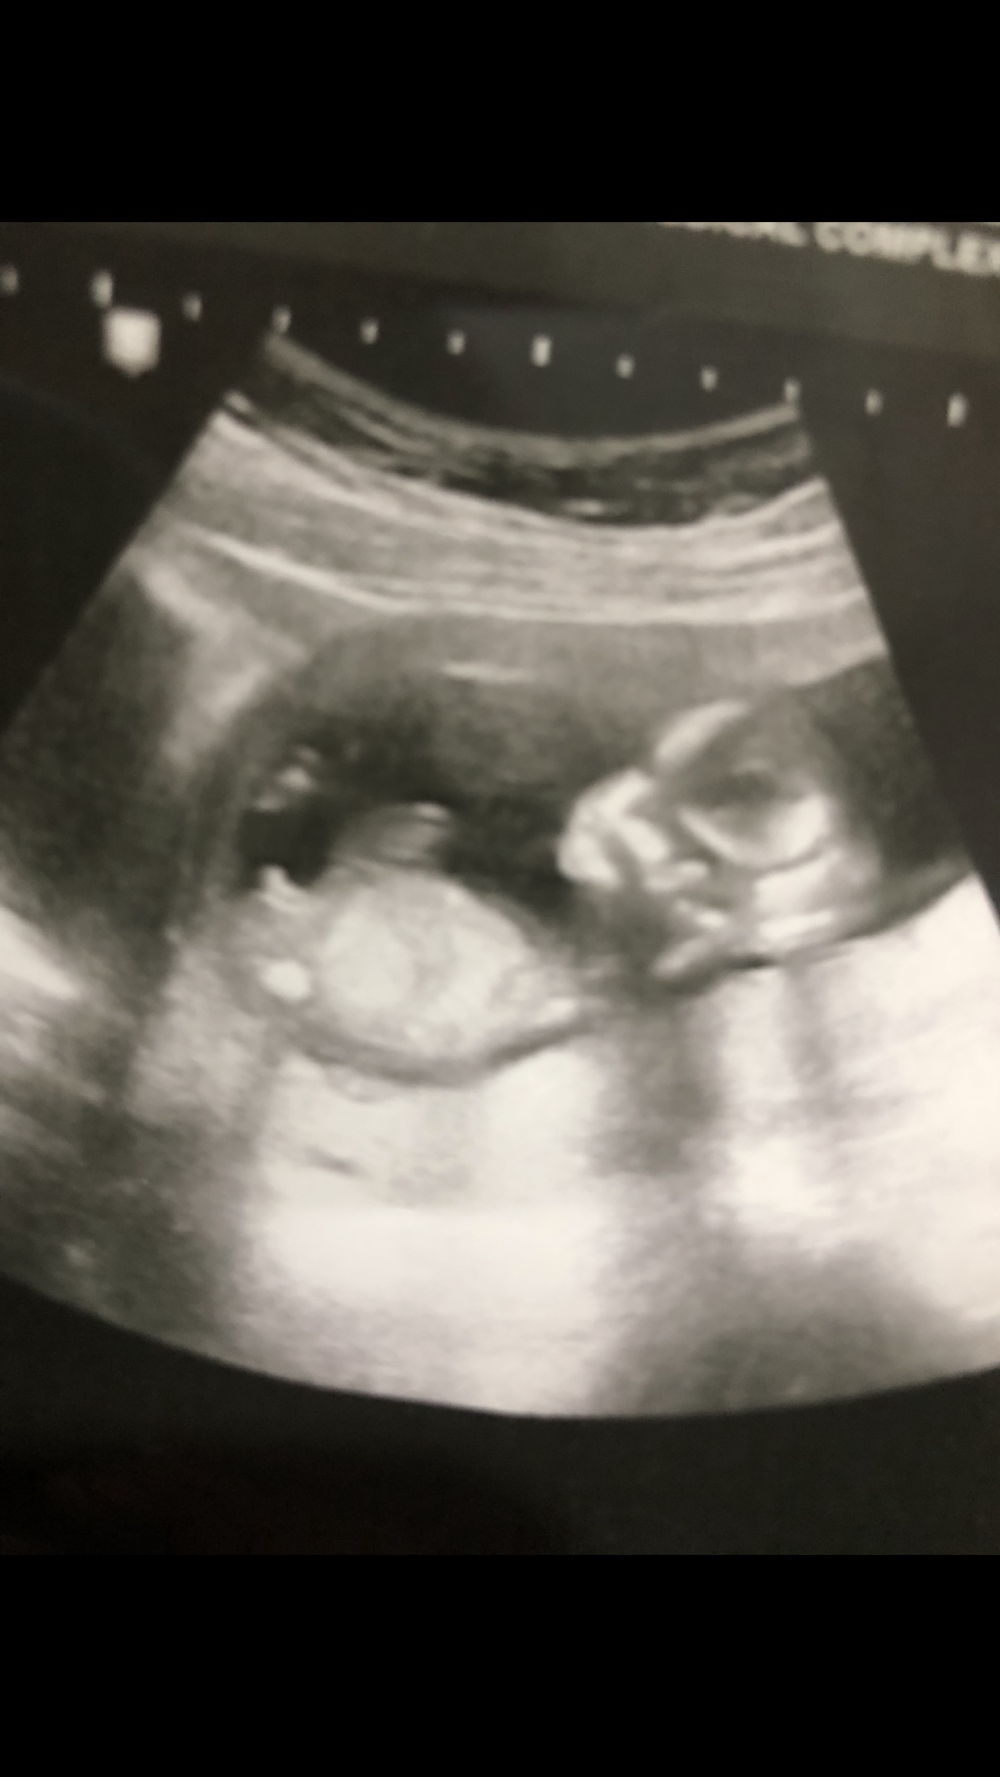

انا سويت مرتين سونار وكلها قالو ولد وفجاءه قالو بنت شوفوالسونارات

السلام عليكم ورحمة الله كيفكم انا سويت مرتين سونار وكلها قالو ولد وفجاءه قالو بنت شوفوالسونارات

اشوف انه ولد متى قالولك بنت؟

بعد اسبوع قالت بنت